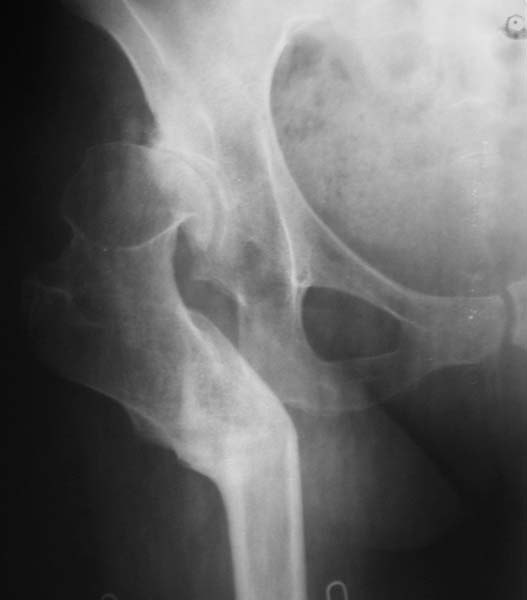

Наше общее мнение - проведение клиновидной остеотомии в зоне дополнительной точки опоры с ее иссечение и укорочением бедра, протезирование ножкой Вагнера.

Похожий случай представляем на ретгенограммах. Операция выполнена в 1996 г.